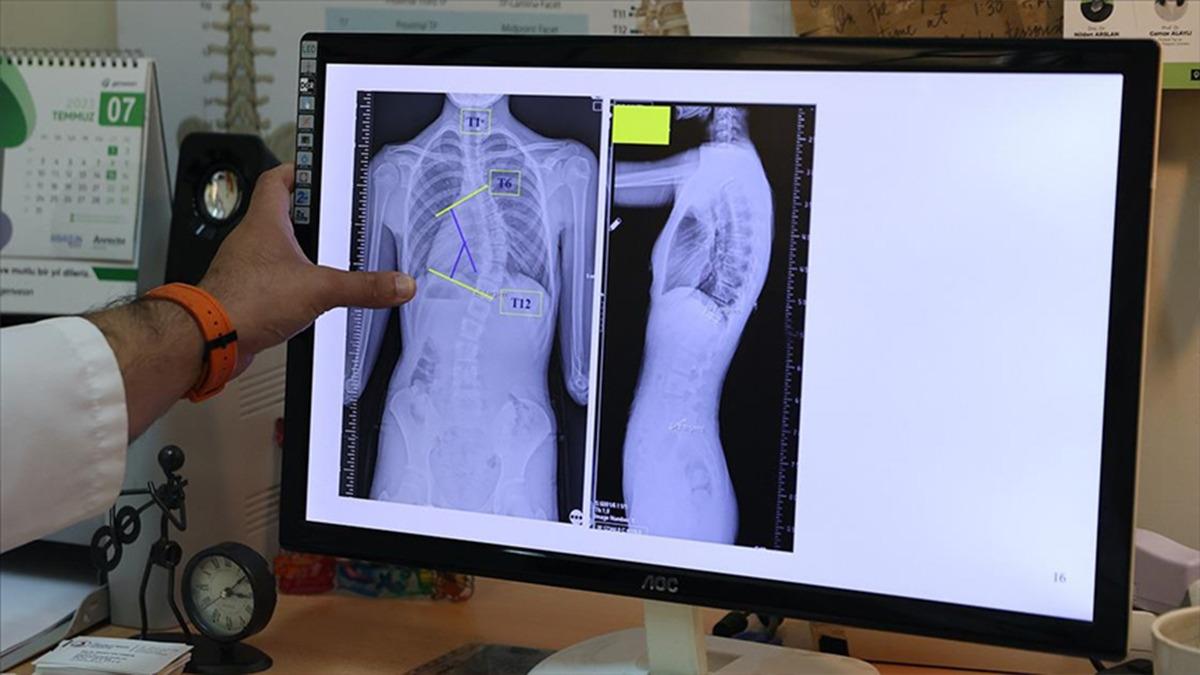

Erdem, tanı sürecine ilişkin de bilgiler vererek, "Skolyozun kesin tanısı ayakta çekilen bir röntgen filmiyle konur. Ancak öncesinde basit, hızlı ve etkili bir tarama yöntemi olan öne eğilme testini kullanıyoruz. Çocuk öne eğildiğinde kaburgalar veya bel bölgesindeki asimetri çok daha net şekilde görülür" şeklinde konuştu.

"Biz 10 dereceye kadar olan eğrilikleri skolyoz olarak değil, asimetri olarak kabul ediyoruz. 10 ila 20 derece arasındaki eğriliklerde çoğu zaman herhangi bir tedaviye gerek duyulmuyor ancak çocuğun yaşı ve büyüme potansiyeline bağlı olarak düzenli takip yapılması gerekiyor. 20 ila 40 derece arasındaki eğriliklerde ise egzersiz programları ve korse tedavileri ön plana çıkıyor. 40 derecenin üzerindeki eğriliklerde, çocuğun yaşı da göz önünde bulundurularak cerrahi tedavileri değerlendirmeye alıyoruz. Günümüzde 40 ila 50 derece arası bir gri zon olarak kabul ediliyor. Ancak 50 derecenin üzerindeki eğriliklerin mutlaka tedavi edilmesi gerekiyor."